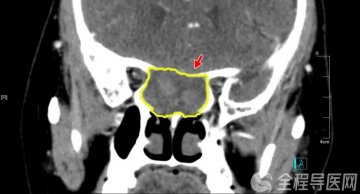

徐州一院肝胆脾胰多学科诊疗团队诊疗疾病范围涵盖各类复杂疑难的肝肿瘤(原发性肝癌、继发性肝癌、肝血管瘤等),肝脓肿,肝囊肿,慢性肝病,胆囊结石,胆管结石(肝内胆管结石、肝外胆管结石),急慢性胆囊炎,胆道肿瘤(胆囊息肉、胆囊癌、胆管癌),急慢性胰腺炎,胰腺囊肿,胰腺癌,胰腺内分泌肿瘤,脾肿瘤,脾功能亢进,脾肿大等。